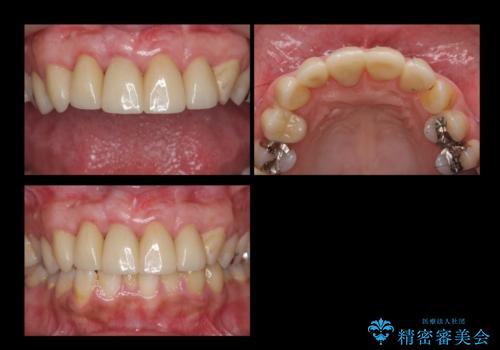

- 前歯の被せもののやり直しを希望して来院。

隣の歯もつぎはぎでプラスチックが劣化していたため、虫歯を取りセラミックでかぶせました。

保険治療の前歯の被せものの縁(マージン)が歯茎の中まで及んでいたため、歯周外科手術を行い、マージンが歯肉縁下深くならないように設定しました。

- 63.8万円(右上4~左上2:emaxクラウン 7万円x6本、仮歯 1万円x6本、歯周外科手術 15万円、右上1:精密根管再治療 9万円およびファイバーコア2万円)費用は治療当時の料金となります

右上1番は、根の治療のやり直しをしています。